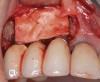

Because the osteotomy created by the trephine is wider than the originally placed implant, it may be challenging to immediately replace this implant unless there is sufficient apical bone available for implant stabilization. For some cases, a wider implant can be placed, but the physiologic rules requiring 1.5 to 2.0 mm for tooth/implant or 3.0 mm for implant/implant spacing,2 as well as other established esthetic criteria, must be respected. For example, a clinical examination revealed a fractured implant in the position of tooth No. 14 along with a fracture to tooth No. 13 (Figure 4). After trephine removal of the fractured implant and extraction of the fractured bicuspid, two implants were placed (Astra Tech, Dentsply Sirona), utilizing apical and axial bone in the apical third of the osteotomy and alveolus to stabilize both fixtures (Figure 5). When this cannot be performed, a staged approach should be employed wherein the site is augmented to facilitate implant placement 4 to 6 months after explantation and grafting.

(4.) The implant in the molar position was relatively narrow and failed biomechanically. It was removed with a trephine, and the adjacent fractured bicuspid was also extracted to accommodate an implant. Because sufficient apical bone was present, a wider implant was placed in the molar position. Bone augmentation was performed around both implants.

Figure 4

(5.) The implant in the molar position was relatively narrow and failed biomechanically. It was removed with a trephine, and the adjacent fractured bicuspid was also extracted to accommodate an implant. Because sufficient apical bone was present, a wider implant was placed in the molar position. Bone augmentation was performed around both implants.

Figure 5